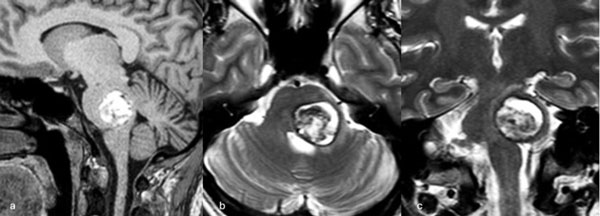

Figura 2. RM postquirúrgica de encéfalo. Se evidencia una exéresis completa, sin lesión de estructuras adyacentes. A) Imagen ponderada en T1 posterior a la administración de gadolinio, corte axial. B) Imagen ponderada en T2, corte axial.

Figura 8. RM postquirúrgica de encéfalo. Se evidencia una exéresis completa, sin daño del parénquima adyacente. A, B y C) Imágenes ponderadas en T2 en cortes coronal, axial y sagital, respectivamente.